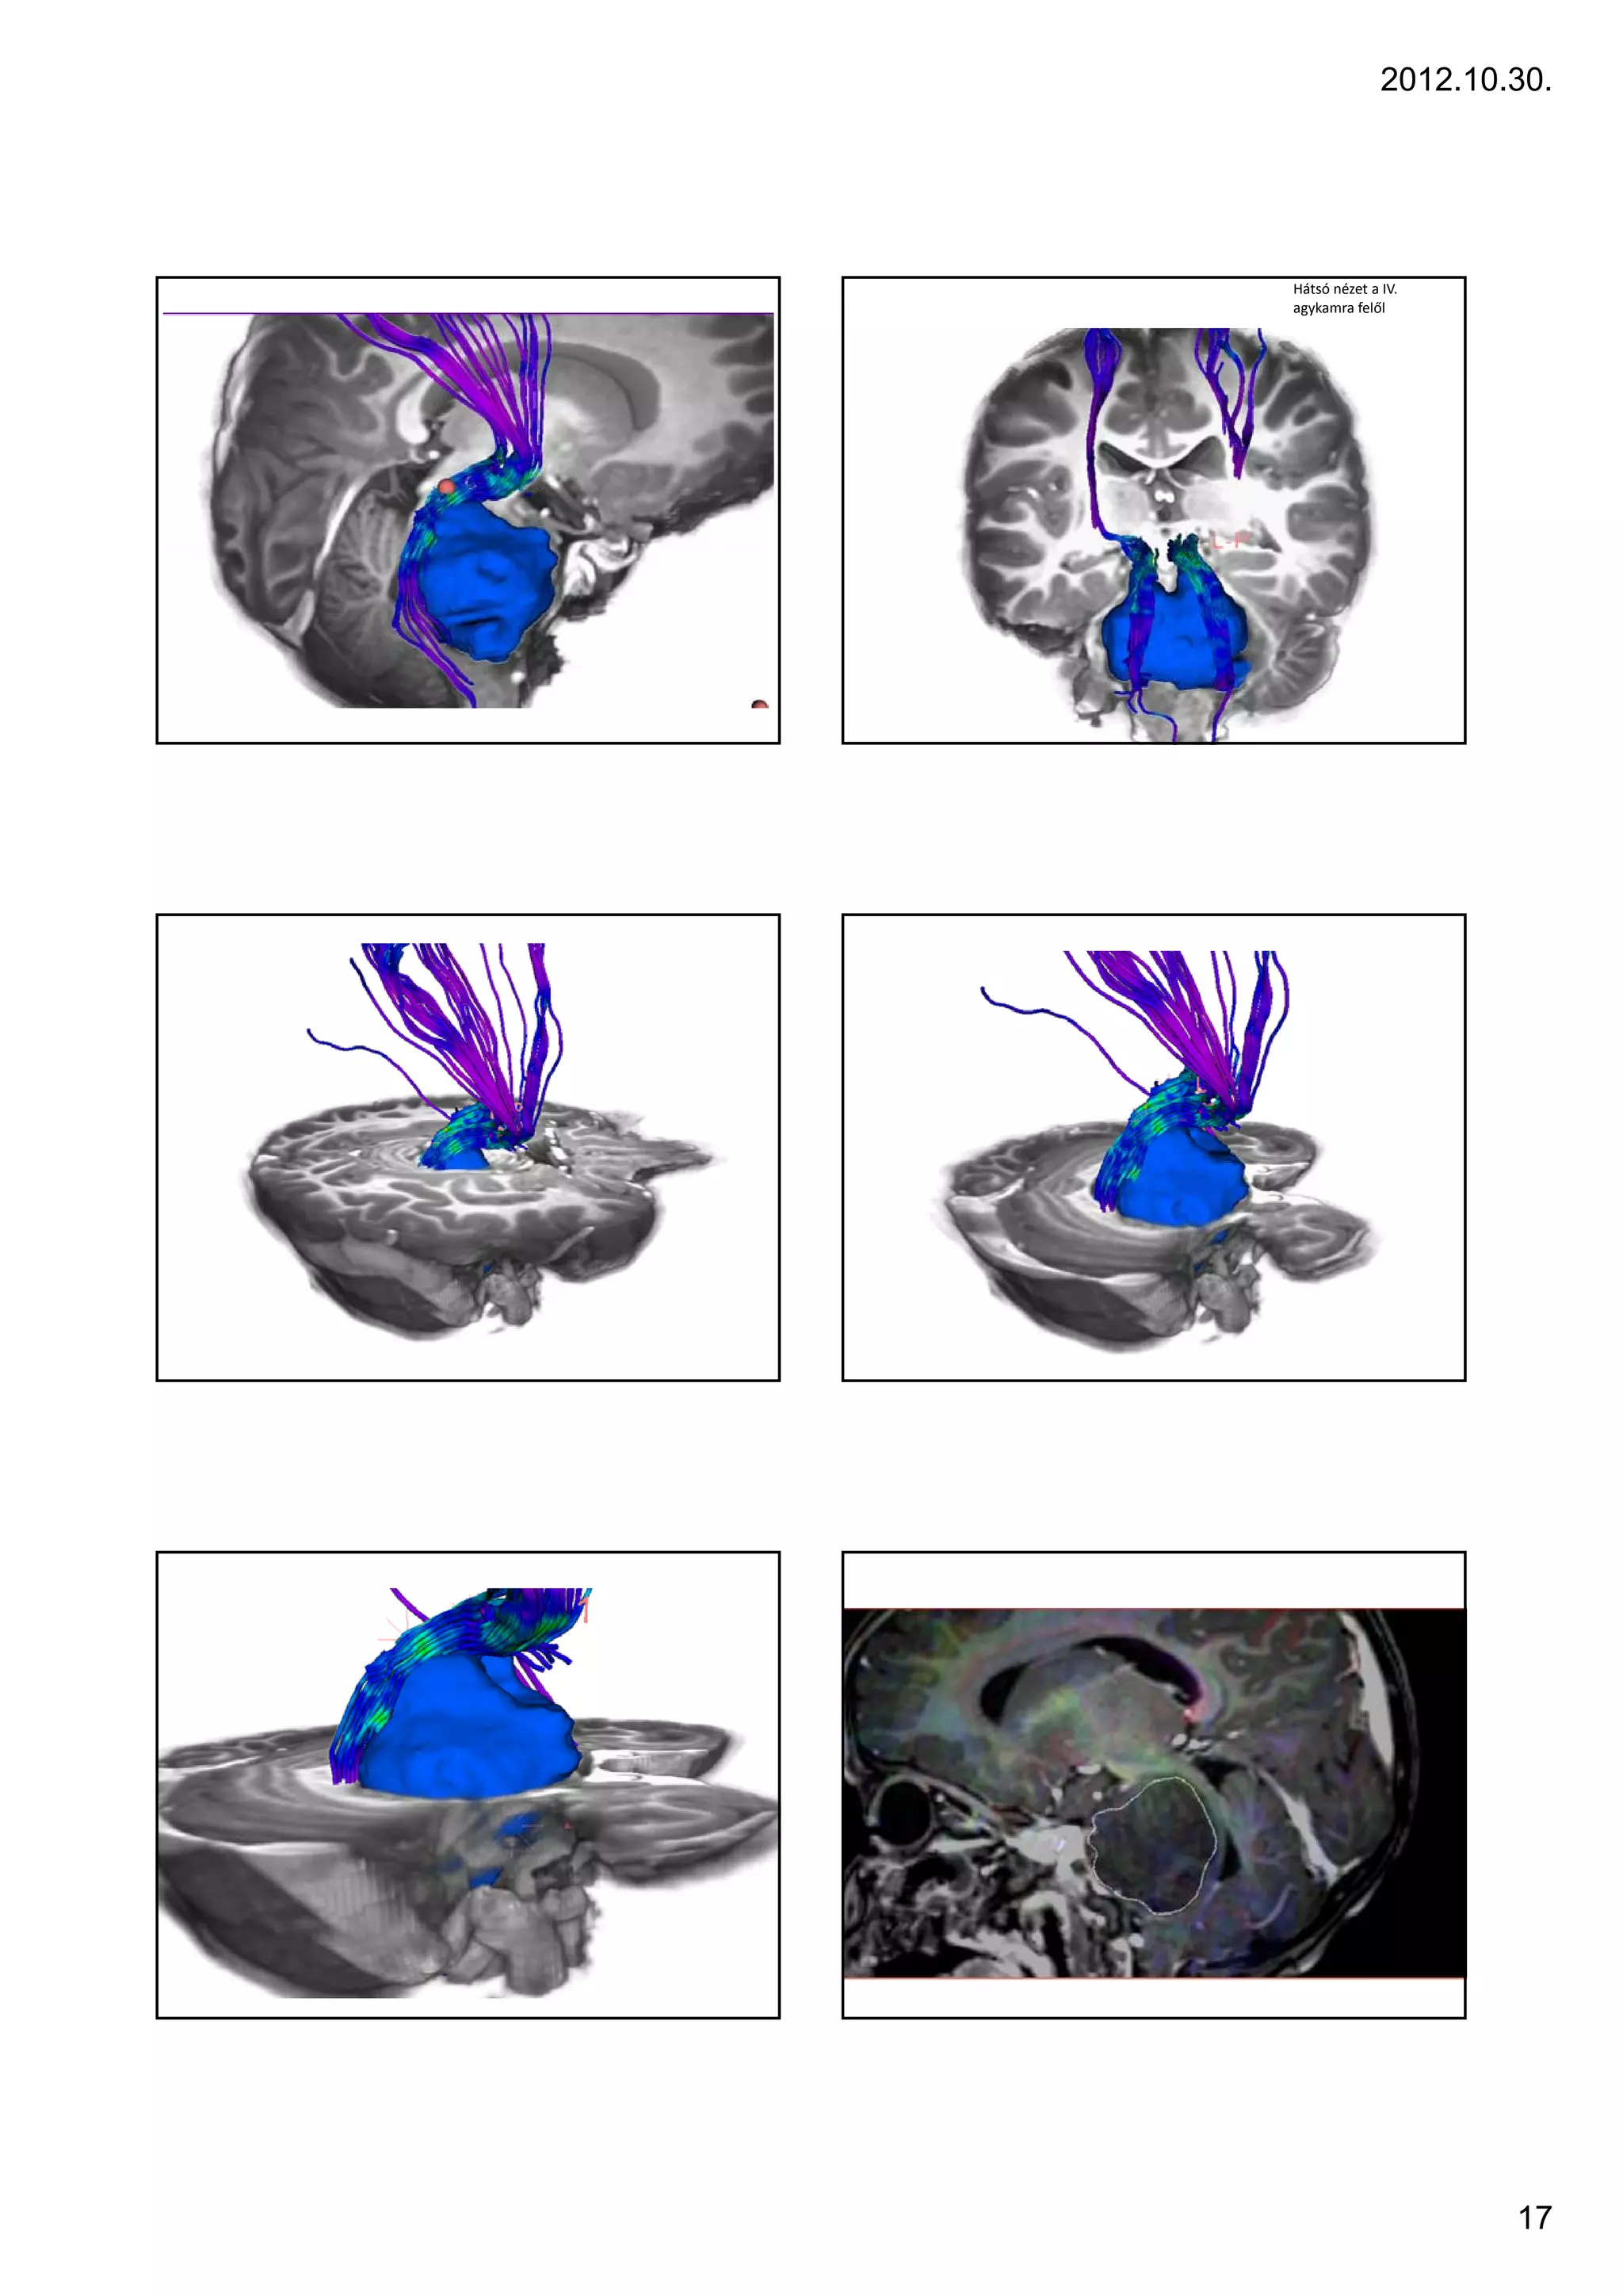

Hátsó nézet a IV.

agykamra felől

arise from the midbrain or medulla.                                                3 yr, F, ICP signs, cerebellum – tonsillar herniation